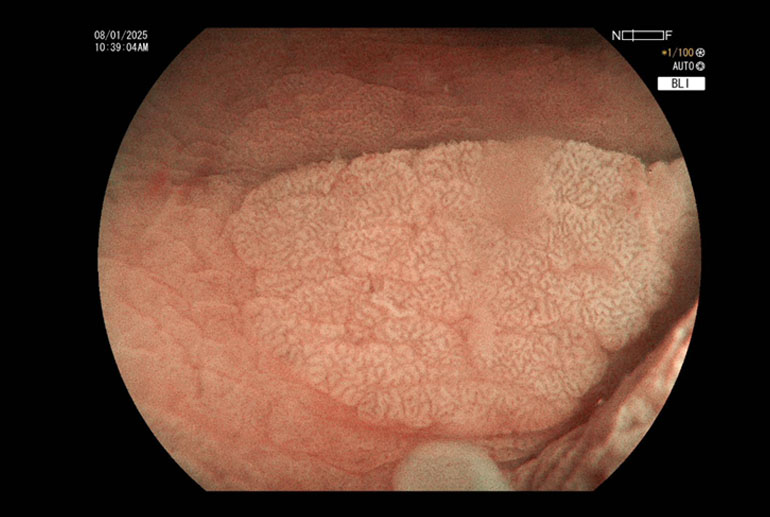

Polyps seen using image enhancement (Blue Light Imaging)Polyps seen using image enhancement (Blue Light Imaging)

Performing the same procedure under water is now recognized to offer additional advantages. In this technique then a polyp is detected, air is sucked out of the colonic lumen and approximately 300 to 400 mL of water is infused. The entire procedure of snaring and resecting the polyp is then done under water immersion. Water acts as a natural magnifier hence mucosal details of the polyp are much more clearly visualized. Most polyps tend to float in water due to their fat content and this leads to a natural separation of the polyp from the underlying submucosal layers. This makes it easier to grasp the polyp by snare and to resect it with less possibility of causing a perforation.

Our patient had multiple polyps ranging between 7mm to 15 mm. Most of the polyps were flat, classified as Paris to AA. Several of these polyps were situated in cecum and ascending colon where colonic wall is quite thin and risk of perforation is higher. Using the technique of hydraulic immersion, it was possible to remove all these polyps with minimal risk to the patient. Post polypectomy site of the largest removed polyp was seen to be oozing blood; this was sealed with application of 3 hemoclips; effective hemostasis was achieved and patient did not suffer any complications.